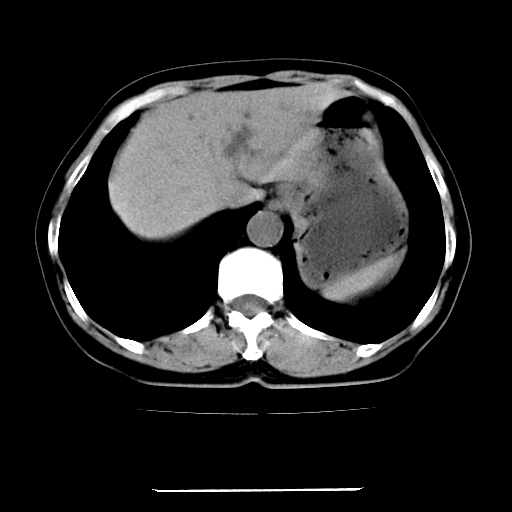

标题: CT22301:女,67岁,上腹部疼痛一周伴皮肤黄染,无发热。 [打印本页]

女,67岁,上腹部疼痛一周伴皮肤黄染,无发热。

左叶肝内胆管结石,并远端肝内胆管扩张。

考虑:肝内胆管结石继发肝内胆管扩张,右肾旋转不良。

支持肝内胆管结石并肝内胆管扩张。

肝内外胆管结石并肝内胆管扩张。

建议薄层观察,除外肝门部胆管细胞癌

考虑肝胆管癌;胰头占位?【形态失常,体积增大】

1、肝门高密度影下层面和胰头层面可见轻度胆管扩张,而静脉和延迟期均未见扫描完胰头,不能完全排除胰头占位。2、肝门部高密度影,考虑钙化或结石。

考虑肝门胆管癌伴门脉左支受侵包埋,建议mrcp进一步检查。